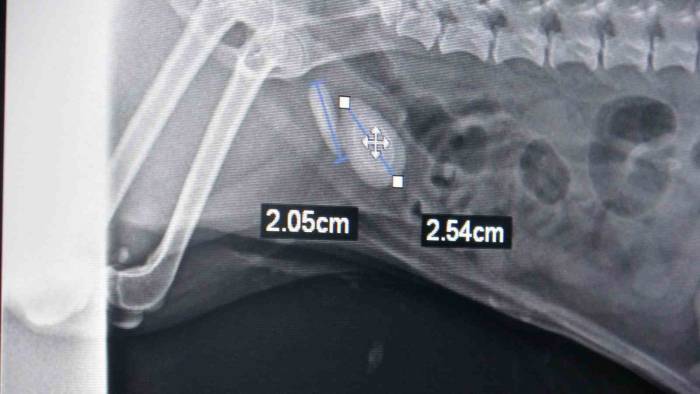

Tokat'ta bir evcil hayvan sahibi köpeğinin idrar yapamaması, idrardaki renk değişiklikleri, idrarda kan olması, idrara gitme isteği ama idrarını yapamaması şikayetleriyle veteriner hekime başvurdu. Yapılan muayenelerin ardından köpeğin idrar kesesinde taş olduğu tespit edildi. Yapılan operasyonla köpeğin idrar kesesindeki üç taş çıkarıldı. Ameliyatı gerçekleştiren veteriner hekim Muhammet Ahmet Gülden, "Evcil hayvan idrar yapamama şikayetiyle kliniğimize başvurdu. Yaptığımız ultrason muayenesinde taş tespit ettik. Ondan sonra yaptığımız röntgen muayenesi ile taşı tam olarak teşhis edip, ameliyat kararı aldık. Toplam teşhis ettiğimiz taş iki taneydi ama ameliyat yaptığımızda üç tane taş çıkardık. 2 buçuk, 2 ve 1 santimetrelik bu taşları sistotomi ameliyatıyla aldık. Ameliyat olan evcil hayvan terrier ırkı, 7 veya 8 yaşında bir köpek. Sürekli tuvalete gidip idrarını yapamama şikayetiyle geldi. İdrar kesesinin yankısı, idrarda taş kristaller, kum, enfeksiyon hastalıkları, bunlar da benzer şikayetlerle olabiliyor. Tabii hasta sahibinin bunu anlayabileceği en önemli belirti idrardaki renk değişiklikleri, idrarda kan olması, idrara gitme isteği ama idrarını yapamaması. Evcil hayvan sahiplerinin bu durumla karşılaştıkları zaman ilk yapması gereken şey fazla zaman kaybetmeden bir veteriner hekime başvurmaları olmalıdır. Hayvanın uzun süre idrarını yapamaması böbrek yetmezliğine sebebiyet veriyor. Böbrek yetmezliği ölüm durumuna kadar götüreceği için hayati risk oluşturuyor. Bazı hayvanlarda yatkınlık var. Bazı ırklarda taş oluşması ile alakalı yatkınlıklar var. Onun dışında beslenme bozuklukları gibi olgular da etkili olabilir. Erkek hayvanlar dişi hayvanlara göre taş ve idrar kesesi yangısına daha yatkındır. Kediler ve köpekler, özellikle kısırlaştırılmış olan hayvanlar mutlaka kısır kedi mamaları yemeleri gerekiyor. Bunlar dışında hazır su tüketmeleri de önemli bir durumdur. Çeşme suyundan ziyade hazır su daha sağlıklı olacağından, bunlara dikkat etmeleri daha iyi olur. Şu an ameliyat olan köpek iyi durumda, idrarını yapabiliyor" dedi.